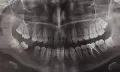

Давно нет коренных зубов, пришел к одним стоматологам они сказали, полечим, обточим и поставим протез. Пришел к другому он сказал, что поставлю временные съемные протезы без обточки зубов, т.к. необходимо восстановить челюстные суставы (слышны щелчки при открывании челюсти), то есть походить с ними около 3-4 месяцев еженедельно приходя к нему для подточки то бишь корректировки в том числе и прикуса. Многие протезисты говорят, что все это бесполезно и пустая трата и денег и времени, третий врач сказал, полечу, обточу, и если хочешь, то поставлю не постоянный протез из металлокерамики, а пластмассу. Будешь приходить ко мне также раз в неделю для обточки, хотя все это туфта (его слова).